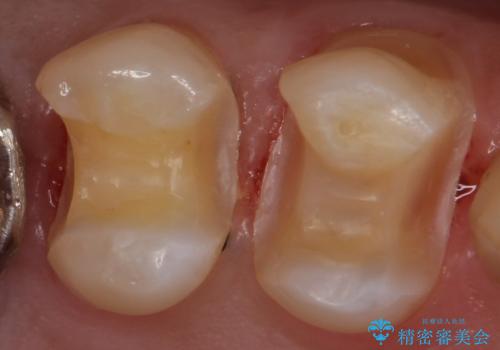

銀の詰め物を除去し、残った歯の量が多かったためセラミックインレーでの修復となりました。

歯の内側に詰めるインレーでの修復でも、形によっては外から見える場合があります。

適合の良いセラミックインレーにやり替えることで外から見た時の違和感がなくなります。

また今回は治療前の写真で食べ物が詰まっている様子が伺えますが、適合がよく段差のない修復をすることで食べ物が詰まることを減らし、結果的に虫歯のリスクを下げることも期待できます。